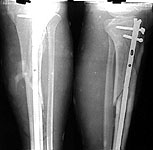

I elected to do closed interlockingnailing - the operation I am most comfortable with. The skin was blisteredthroughout the leg so open plating was not an option nor conservative treatmentas dressings would have been a nightmare in plaster.

I used Indian madetibial nail ($30!), customised it by decreasing the herzog bend and adding twomore holes in the nail proximally which I locked with free hand technique.

The post op xray is attached.

Very good! (at that price I want to buy 100 tibial and 100 femoralnails!)

Nice case, and nice result (early). Where can we order some of those $30.00nails?

i rest my case. good job.